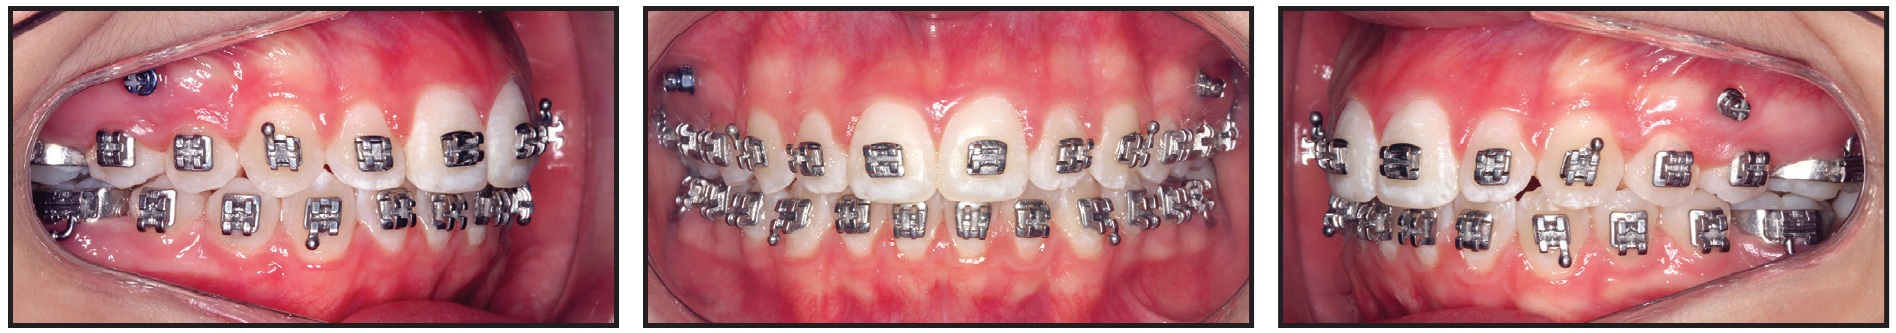

After seven months of treatment, the initial alignment was complete. A bracket-head mini-implant (1.5mm × 8mm, with a 1mm transmucosal collar) was inserted on each side between the upper premolars to provide skeletal anchorage for the DAVIT device (Fig. 7). The right and left mini-implants had counterclockwise and clockwise thread directions, respectively, to prevent screw failure due to the rotational force load.35 The posterior power arms of the DAVIT were activated above the .019" × .025" alignment archwire to produce a posterior intrusive force of about 300g per side. The anterior power arms were activated below the archwire to produce an anterior extrusive force of about 150g on each side, for a total 300g of anterior extrusive force. The horizontal anchorage segments of the DAVIT were tied into the mini-implant bracket slots with .008" stainless steel ligature wire. Finally, the activated vertical plugs at the ends of the horizontal power arms were inserted into the vertical slots of orthodontic cross-tubes positioned between the lateral incisor and canine and between the second premolar and first molar on each side of the maxillary arch.

Fig. 7 After seven months of alignment, mini-implants inserted between upper premolars, and DAVIT appliances activated to correct open bite by posterior intrusion and anterior extrusion.

After two months of treatment with the DAVIT appliance, the open bite was completely closed and interocclusal contact between the premolars had substantially increased (Fig. 8).

Fig. 8 After two months of DAVIT treatment, open bite closed and vertical relationship between premolars substantially improved.